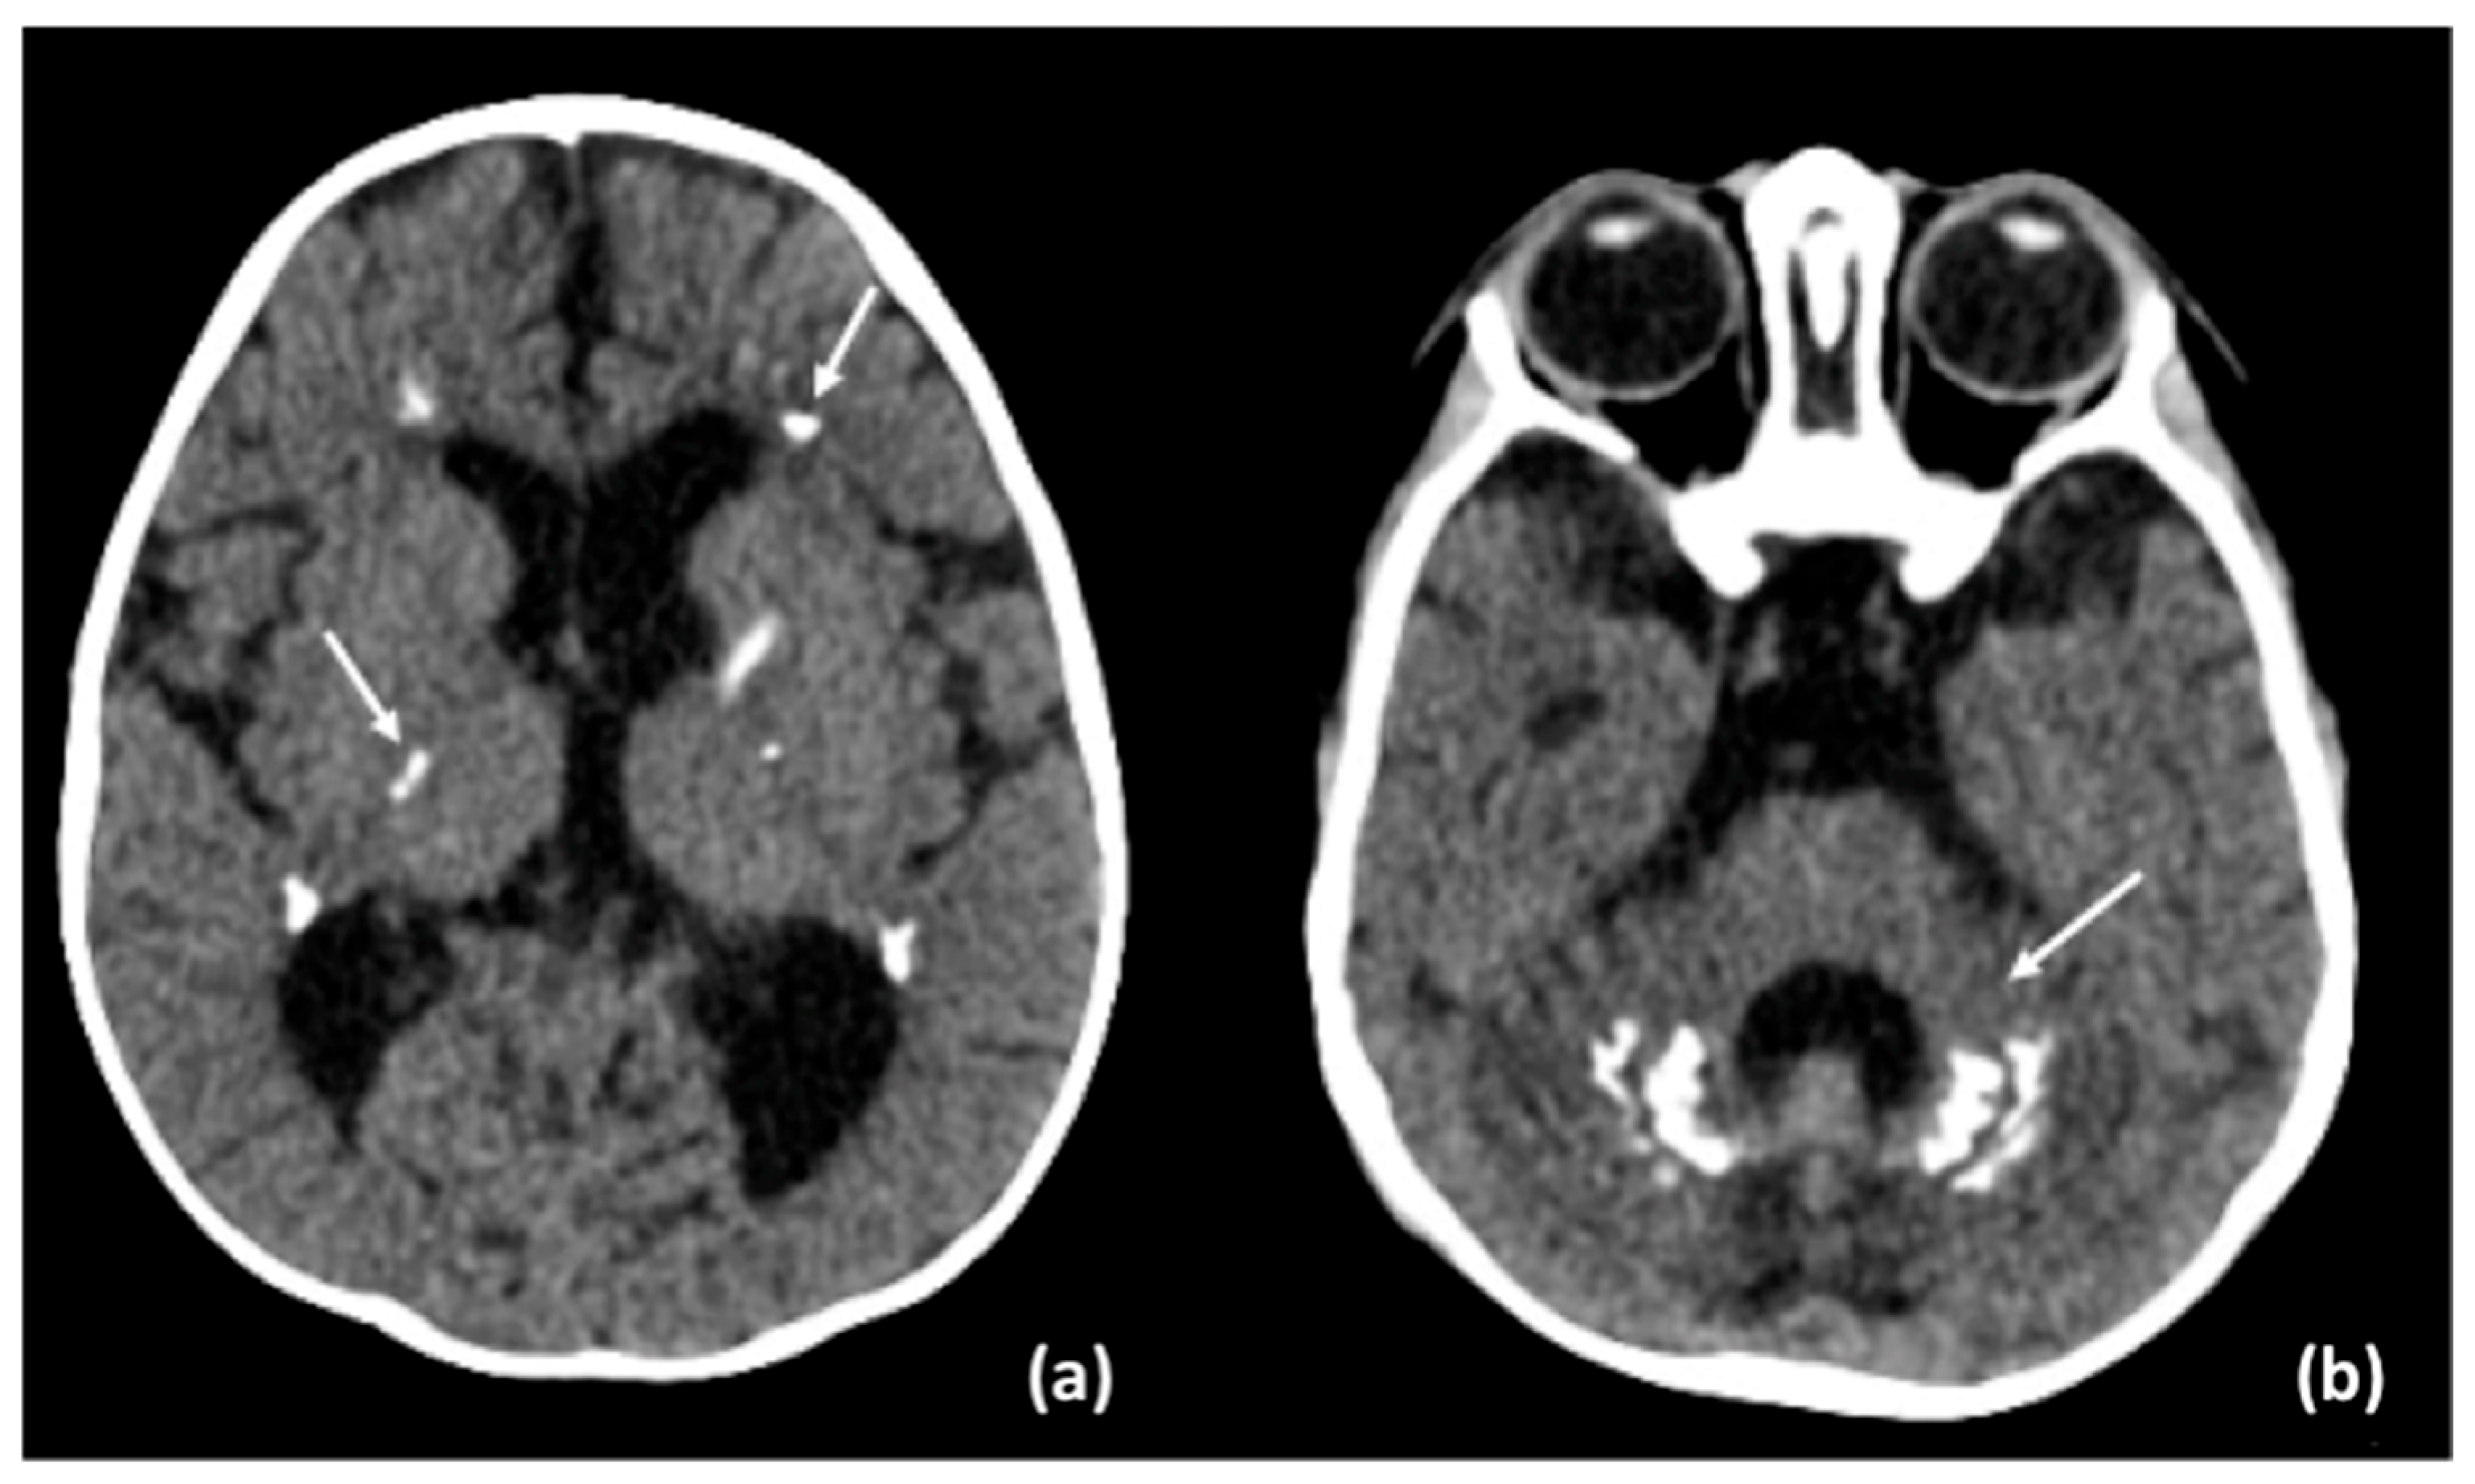

3.2. Results of Imaging Data